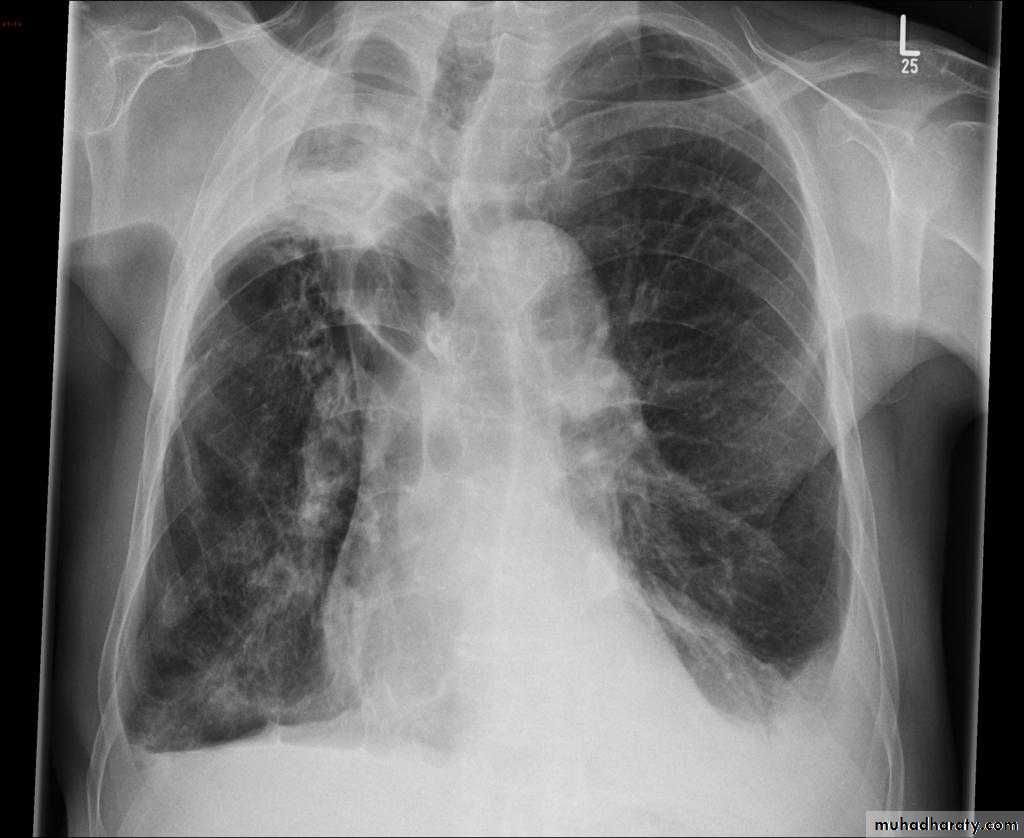

Post primary TB radiographic appearance

Post-primary pulmonary tuberculosis, also known as reactivation tuberculosis or secondary tuberculosis occurs years later, frequently in the setting of a decreased immune status. In the majority of cases, post-primary TB within the lungs develops in either :

* posterior segments of the upper lobes

*superior segments of the lower lobes

Typical appearance of post-primary TB

1.patchy consolidation or poorly defined linear and nodular opacities in both apices , upper zone in one lung , & lower zone in other lung ( ulternating lesion ) .2. Post-primary infections are far more likely to cavitate with multiple abscess formation & air fluid level more develop in the posterior segments of the upper lobes.

3. Tuberculomas seen in post-primary TB and appear as a well defined rounded mass typically located in the upper lobes .

TB abscess